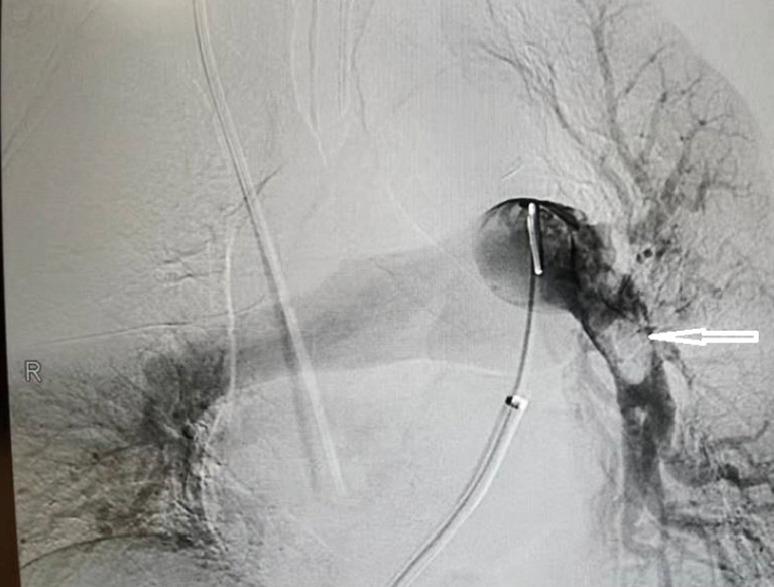

Herein, we report the case of a patient who presented with hypotension and tachycardia accompanied by an asymptomatic right leg deep vein thrombosis, right atrial thrombus, and pulmonary embolus. He had a history of radical resection of colon cancer 1 month prior. And he had developed chest tightness accompanied by stabbing pain in the chest area 1 day ago. He experienced an episode of syncope 8.5 hours ago. So he was referred to the local hospital. After the pulmonary computed tomography angiography (CTA) scan, he was diagnosed with pulmonary embolus and administrated with 5,000 u low molecular weight heparin. Then he was transferred to our hospital. On arrival in the emergency department, the bedside transthoracic echocardiography (TTE) revealed there was an enlarged right atrium and right ventricle, with a floating right atrial mass prolapsing through the tricuspid valve during diastole. The patient accepted anticoagulation treatment, but refused to undergo thrombolysis or surgical embolectomy. Eventually, the right heart thrombi (RiHT) floated to the left main branch of pulmonary artery. It was successfully treated by using AngioJet device and venoarterial extracorporeal membrane oxygenation (VA-ECMO). Our case provides clinical evidence supporting the feasibility and efficacy of AngioJet device and VA-ECMO in the treatment of the RiHT and PE.

在此,我们报告一例患者,其表现为低血压和心动过速,伴有无症状的右下肢深静脉血栓形成、右心房血栓和肺栓塞。他1个月前有结肠癌根治切除术史。1天前出现胸闷并伴有胸部刺痛。8.5小时前发生一次晕厥。因此他被转诊至当地医院。经肺部计算机断层扫描血管造影(CTA)检查后,他被诊断为肺栓塞,并给予5000单位低分子肝素治疗。随后他被转至我院。到达急诊科时,床旁经胸超声心动图(TTE)显示右心房和右心室增大,舒张期有一个漂浮的右心房团块经三尖瓣脱垂。患者接受了抗凝治疗,但拒绝接受溶栓或手术取栓。最终,右心血栓(RiHT)漂浮至肺动脉左主支。使用AngioJet装置和静脉 - 动脉体外膜肺氧合(VA - ECMO)成功对其进行了治疗。我们的病例提供了临床证据,支持AngioJet装置和VA - ECMO治疗RiHT和PE的可行性和有效性。